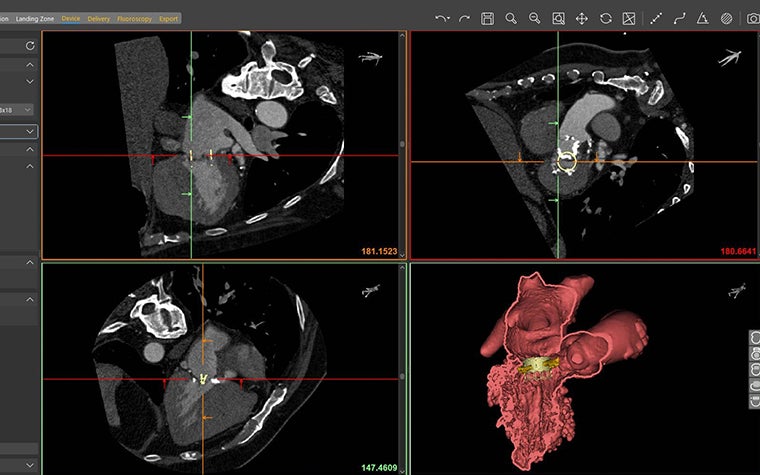

Für Dr. Wang liegt der Wert der 3D-Technologie in der Möglichkeit des computergestützten Designens. Sie erklärt die zwei wichtigen Funktionen der 3D-Modellierung für den Transkatheter-Mitralklappenersatz: Erstens kann per 3D-Druck für jeden Patienten eine passgenaue Klappe hergestellt werden. Zweitens kann durch 3D-Modelle die richtige Position der Klappe ermittelt werden, damit es nicht zu einer Einengung des linksventrikulären Ausflusstraktes kommt.

Der Transkatheter-Mitralklappenersatz gehört zu den schwierigsten und riskantesten Eingriffen in der modernen Medizin. Ohne sorgfältige 3D-Planung ist die Gefahr groß, dass der Patient verletzt wird - möglicherweise sogar tödlich. Wenn eine neu implantierte Klappe den Blutfluss vom linken Ventrikel in die Aorta blockiert, kann es zu lebensgefährlichen Komplikationen für den Patienten kommen. Wird aber schon vor dem Eingriff erkannt, dass die Gefahr einer LVOT-Obstruktion besteht, können Komplikationen verhindert und das Leben des Patienten gerettet werden. Ohne computergestützte 3D- und 4D-Modellierung ist dies jedoch nicht möglich.

Mimics Enlight, with specific structural heart workflows, gives Dr. Wang accurate 3D models for consistency in taking measurements like neo-LVOT to screen patients for TMVR therapy, plan procedures, and determine the appropriate size and positioning of

TMVR devices. Dr. Wang explains their process, “In doing this we can model how and where we put the valve in our patient. So, while they’re at home watching their TV before they come to us, we take their CT scan, implant the valve at various positions, find out what valve size we’re going to use, and figure out what it’s going to be. We calculate the baseline LVOT surface area, what blood flow they live with. And then once we model a valve inside, we see what remainder of the LVOT they have left. And we can provide a cut-off.” The impact, she says, is a patient's life is saved.